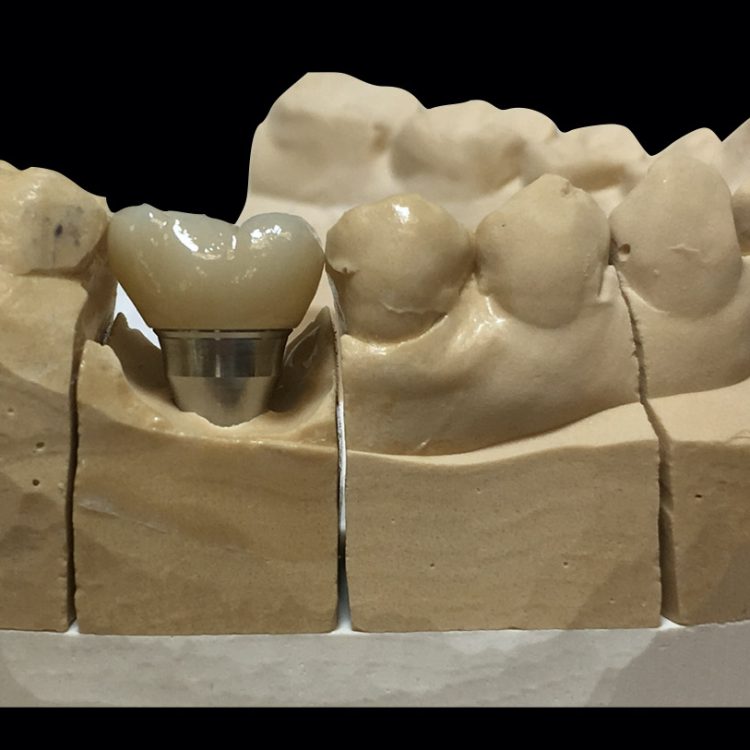

Implantologie

Un implant dentaire remplace la racine d’une dent naturelle et sert d’ancrage à une ou plusieurs dents. On peut donc avoir plusieurs implants intégrés en bouche pour y visser ou coller des éléments prothétiques allant jusqu’à l’arcade complète, fixe ou amovible. Nous fabriquons tous types de prothèses sur implants, selon le besoin du patient et les demandes du dentiste.